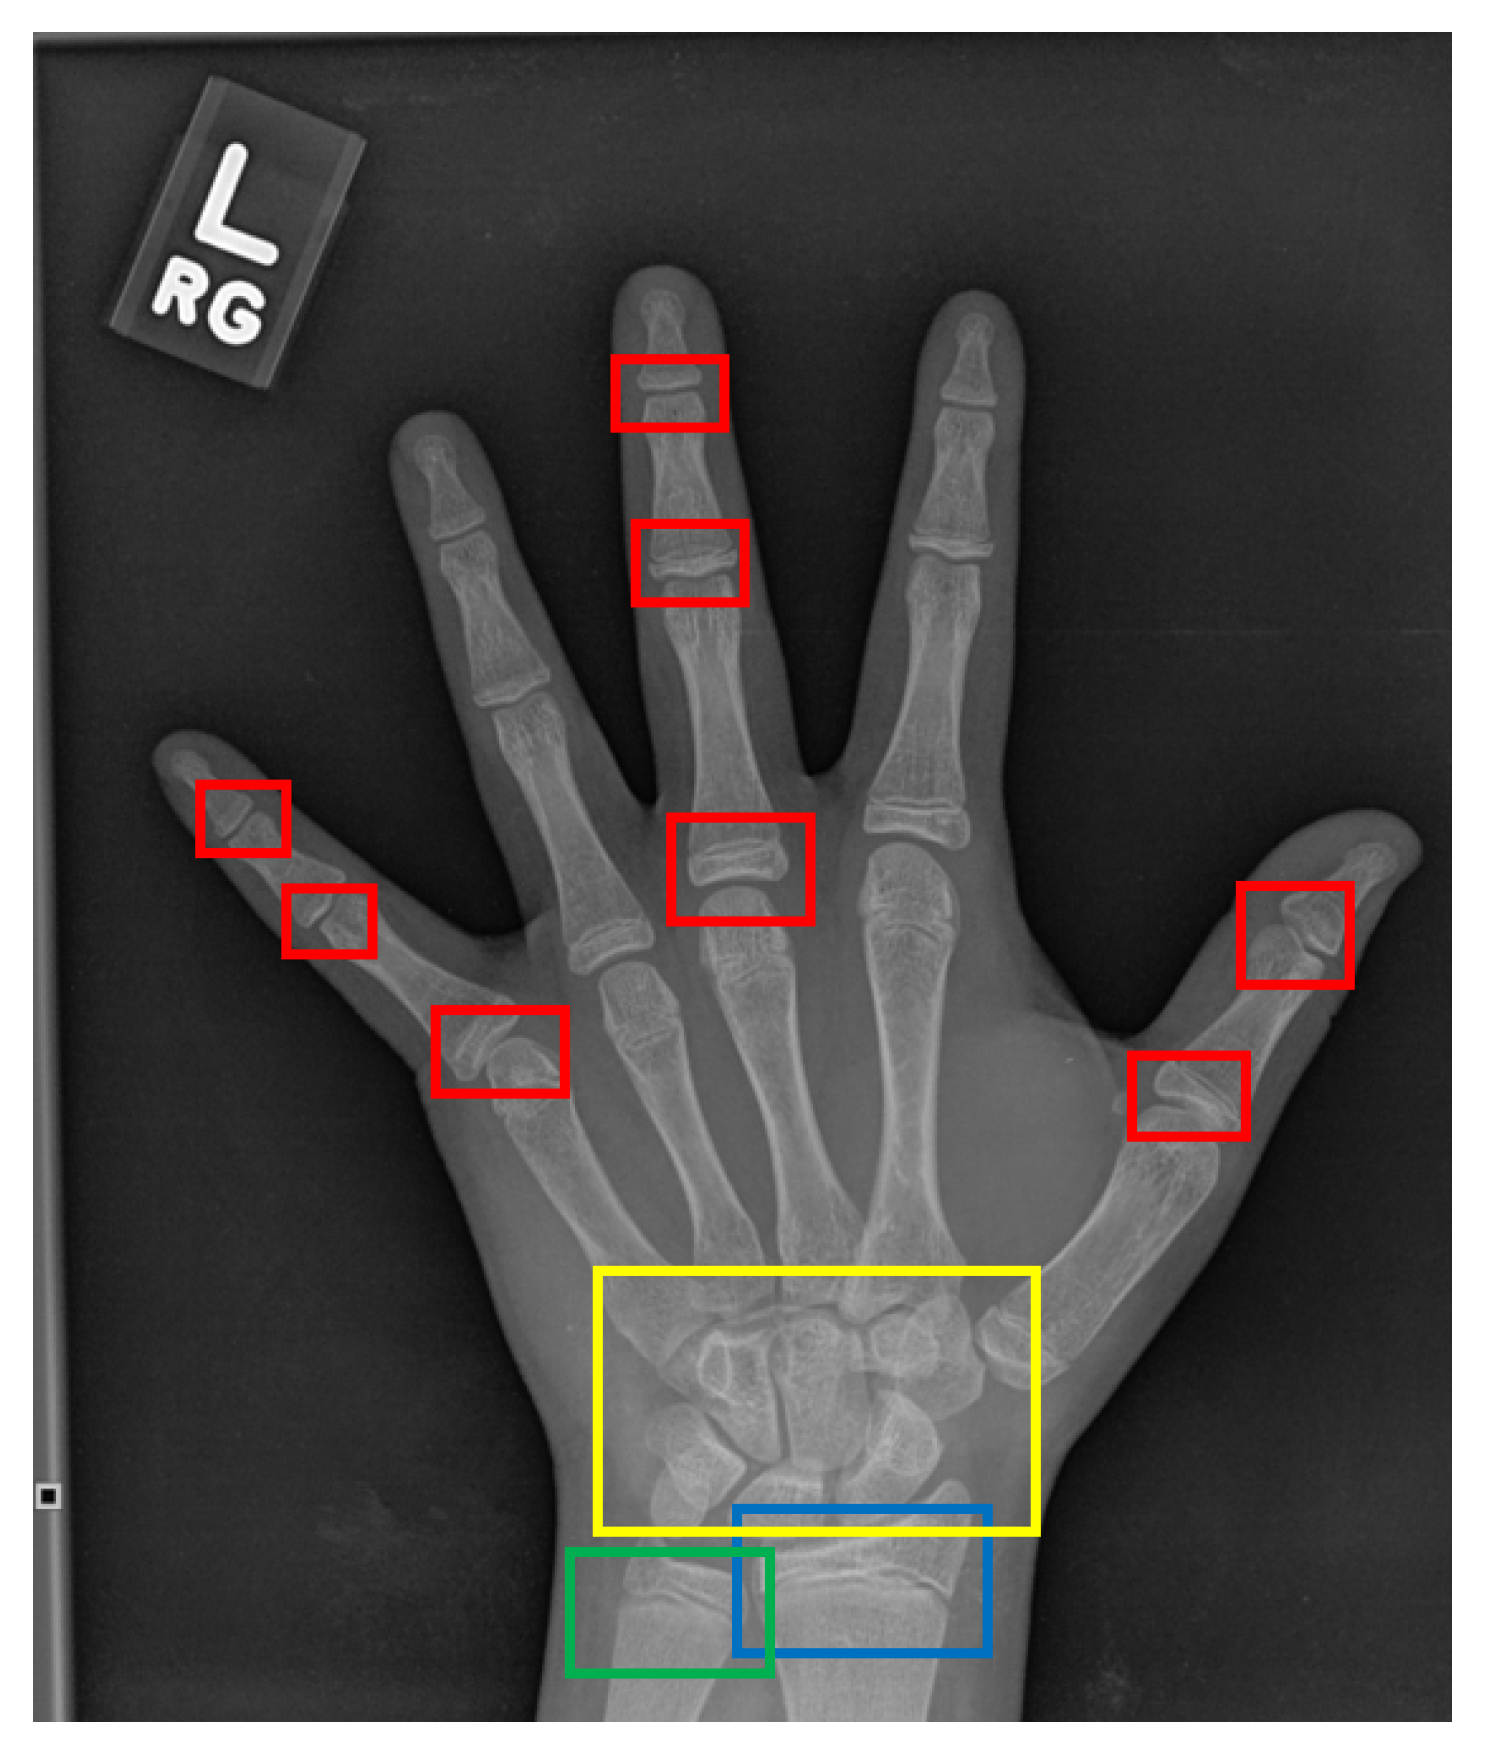

5.5. Results and Discussion: Key-Points Detection